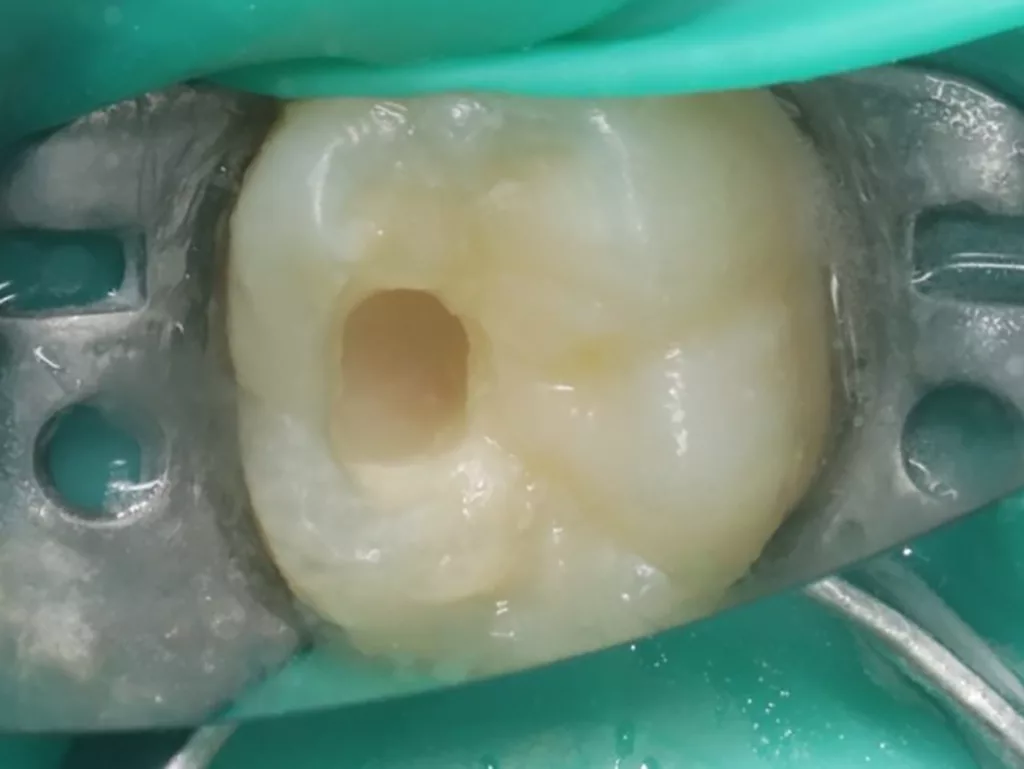

Der PEIR-Defekt schimmerte unter der lingualen Querfissur deutlich dunkler durch (Abb. 21), sodass die Entscheidung getroffen wurde, den Defekt an genau dieser Stelle zu eröffnen (Abb. 22). Das resorbierte intrakoronale Weichgewebe, das die Läsion nur zum Teil füllte, konnte dann gut visualisiert werden (Abb. 22). Kariös verändertes Dentin wurde nicht gefunden. Nach Eröffnung des Pulpahorns sah die Pulpa blass und avaskulär mit Anzeichen einer geringen Blutung aus (Abb. 23). Die komplette Kronenpulpa wurde bis zur Höhe der Kanaleingänge mit einem runden Diamantbohrer unter Wasserkühlung entfernt. Vor und nach der Prozedur wurde die Läsion zuerst mit 1%igem NaOCl und anschließend mit physiologischer Kochsalzlösung gespült. Die Blutung stoppte innerhalb von zwei Minuten vollständig, die Wurzelpulpa erschien gesund, regulär vaskularisiert und sauber (Abb. 24). Es wurde eine reversible Pulpitis diagnostiziert. Die Abdeckung der Wurzelpulpa erfolgte mit einem hydraulischen Kalziumsilikatzement (Rootdent, Technodent), der mit dem Glasionomerzement Fuji II LC (GC, Japan) als temporäre Füllung abgedeckt wurde. Die Platzierung des MTA-Zements wurde abschließend mittels einer Röntgenaufnahme überprüft (Abb. 27). Nach zwei Wochen war die junge Patientin komplett beschwerdefrei. Unter erneuter Trockenlegung mit Kofferdam wurde die adhäsive koronale Restauration mit Komposit Estelite ASTERIA OCE, A2B und Universal Flow AO2 (Tokuyama, Japan) mithilfe eines vorab angefertigten Okklusalstempels erstellt (Abb. 25 und 26). Ein Jahr später kam die Patientin beschwerdefrei zur Nachkontrolle. Das Röntgenbild (Abb. 28) zeigte keinen pathologischen Befund sowie eine physiologische Weiterentwicklung des Wurzelwachstums in Länge und Dicke der Wurzelwände.